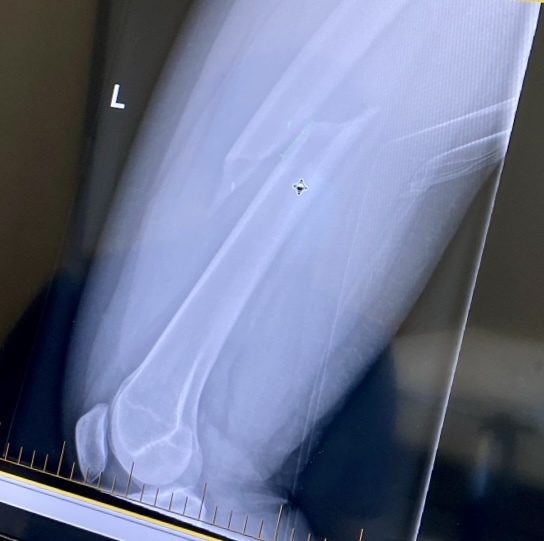

On January 1st 2022, I had one New Years resolution — to run the NY Marathon. And as you may already know…24 days later I broke my left femur skiing.